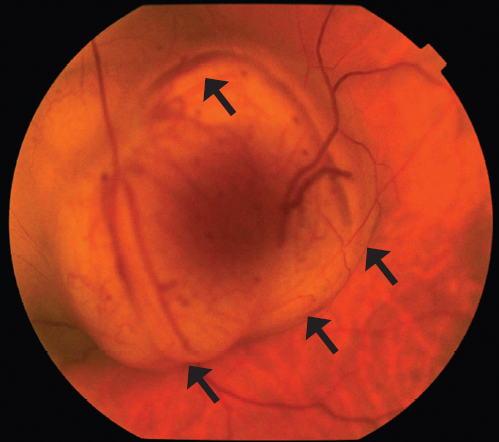

Ophthalmological examination data included examination of the visual acuity of the right eye of 0.8, which was incorrigible and that of the left eye was hand motion. The tonometry result was 18/17 mmHg. Biomicroscopy revealed no abnormalities in the anterior segment of both eyes. Particular attention was paid to the search for Lisch nodules in the iris, which were absent. At ophthalmoscopy, no focal pathologic change was detected in the right eye, while there was a protruding multinodular pink–orange neoplasm in the optic nerve head of the left eye, with clear boundaries, at the base of which, a retinal detachment was visualized in the lower fundus segments (Fig. 2). At the B-scan ultrasound examination, the optic nerve head had a protruding fungiform neoplasm (with height of up to 6.7 mm and diameter of up to 13.0 mm), medium echogenicity, and inhomogeneous density, at the base of which, retinal detachment was observed in the lower fundus segments (Fig. 3). Magnetic resonance imaging of the orbits also confirmed the presence of left eye neoplasm (Fig. 4).

Fig. 2. Astrocytoma of the optic nerve head. Black arrows demonstrate a lobular structure of the tumor

Рис. 2. Астроцитома головки зрительного нерва. Чёрными стрелками указаны выступающие части опухоли